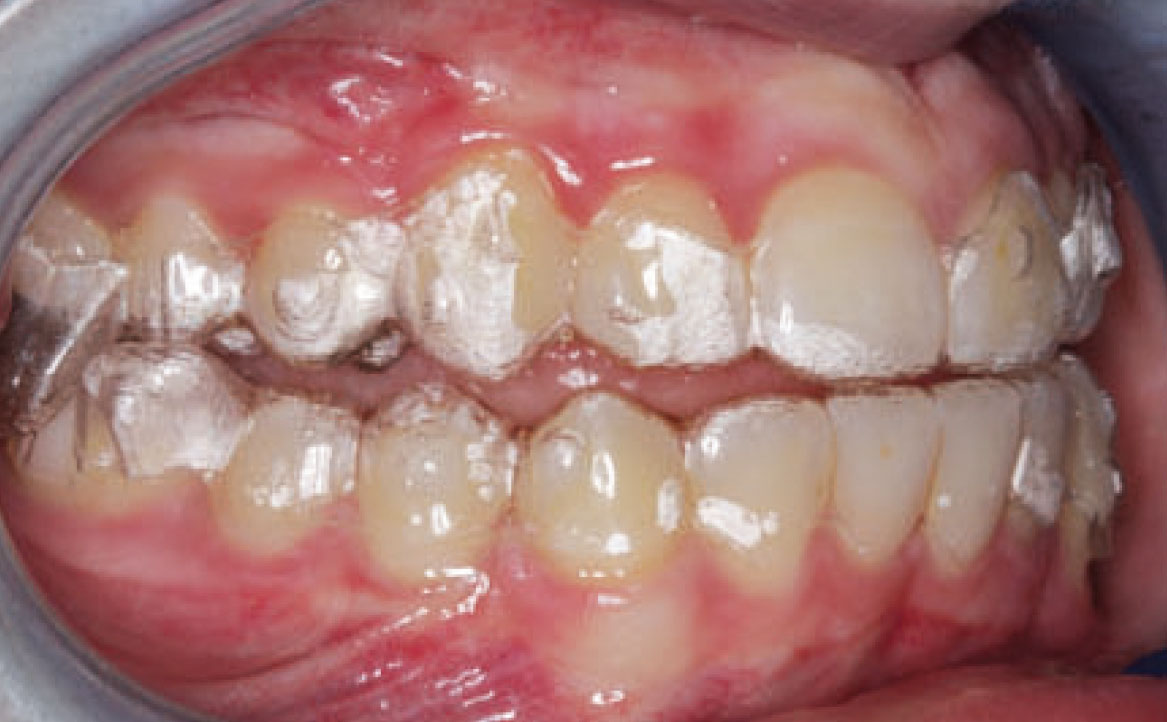

Dall’esame obiettivo intra orale si osservava una seconda classe canina destra e sinistra, una seconda classe molare destra e sinistra, e un diametro inter-canino e inter-molare ridotto sia in riferimento al mascellare superiore sia al mascellare inferiore (fig. 3A-3E).

A seguito del trattamento è stato osservato un miglioramento dell’igiene orale (fig. 5).